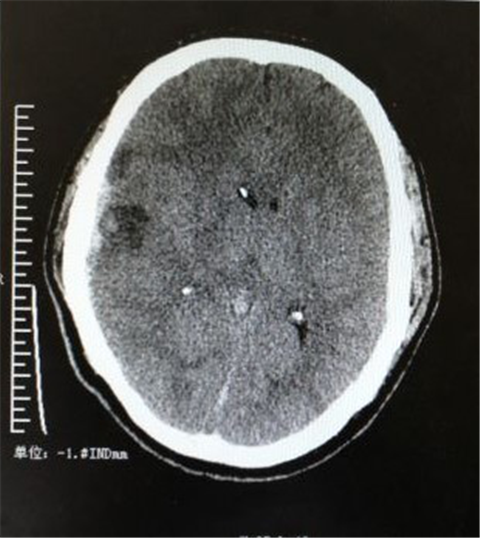

术后CT检查

神经外科主任黎明提出:将经验治疗转变为精准治疗。将1mm大小颅内压探头植入脑室内;即可以引流脑积液/同时监测颅内压力,根据颅内压力决定治疗策略。

当天晚上在向庆勇、文家智医生主刀下立即为患者实施安置颅内压探头置入术,手术顺利,术中观察颅内压为11.3mm Hg,观察半小时后未见颅内压增高。术后送重症医学科继续监控颅内压,此项手术为州医院开展的州内第一列颅内压监测手术。